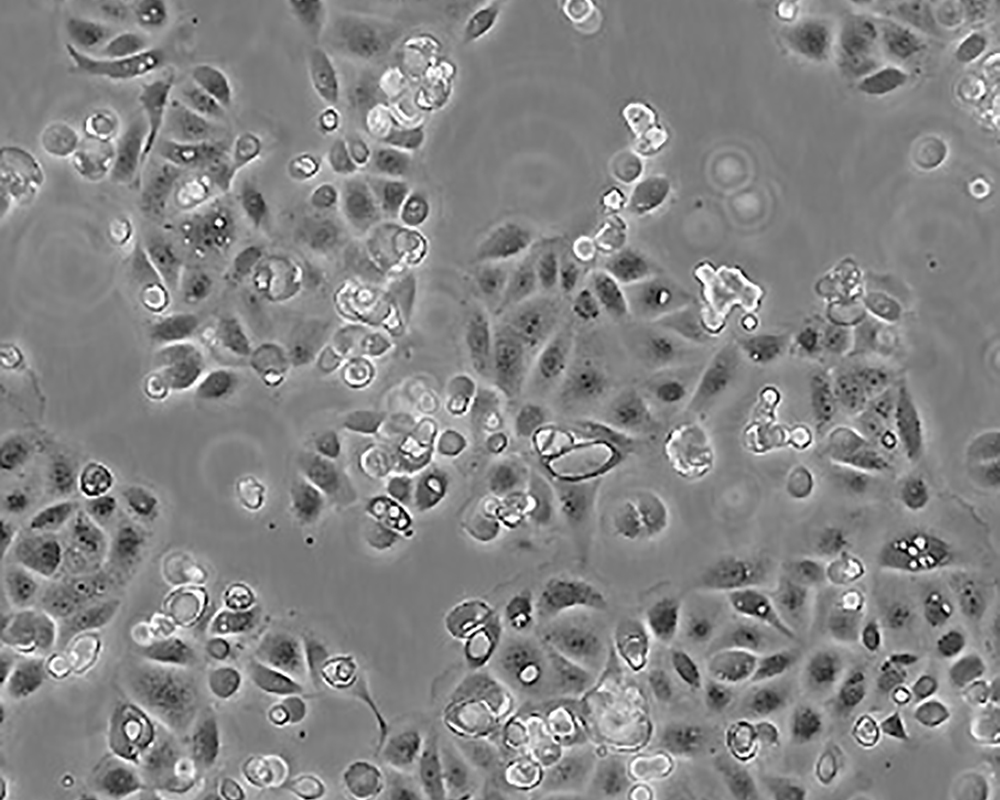

SW 1990

產(chǎn)品名稱 SW 1990

中文名稱 人胰腺癌細胞

形態(tài)特征 epithelial

細胞描述 1978年從胰腺外分泌腺的胰腺腺癌II期患者的脾轉(zhuǎn)移灶中建立了SW 1990細胞株。 報道該細胞的植板率為29%。